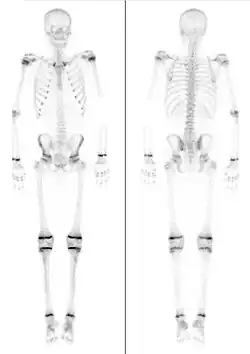

Für die Beurteilung auf Röntgenaufnahmen der am Handskelett des Menschen darstellbaren Epiphysenfugen gibt es spezielle Atlanten, die das chronologische Alter eines Kindes mit dem aktuellen Skelettalter vergleichen lassen (Abb.) Aufgrund der Vielzahl von Wachstumsfugen an den Handknochen, die sich alle zu unterschiedlichen Zeitpunkten knöchern verschließen, ist hier eine Zuordnung in Halbjahresschritten möglich.[4] Damit können, zusammen mit aktuellen Längenmessungen von Körpergröße, Sitzgröße, Beinlänge etc., Aussagen über das noch zu erwartende Gesamtwachstum des Kindes oder des Jugendlichen gemacht werden. Aufgrund der unterschiedlichen Geschlechtsentwicklung bei Mädchen und Jungen ist der Reifungsprozess und damit das Skelettwachstum bei Mädchen früher abgeschlossen. Die ersten Epiphysenfugen schließen sich bei Mädchen um das 14. Lebensjahr, die letzten Fugen beim Jungen nach dem neunzehnten Lebensjahr.

Untersuchungen von Röntgenaufnahmen von zwischen 1915 und 2006 geborenen Kindern haben gezeigt, dass sich der Zeitpunkt, an dem sich die Wachstumsfugen schließen, im Verlauf des letzten Jahrhunderts immer weiter vorverlegt hat und damit – ähnlich wie auch die Pubertät – immer früher eintritt. Der Grund dafür ist nicht ersichtlich.[5]